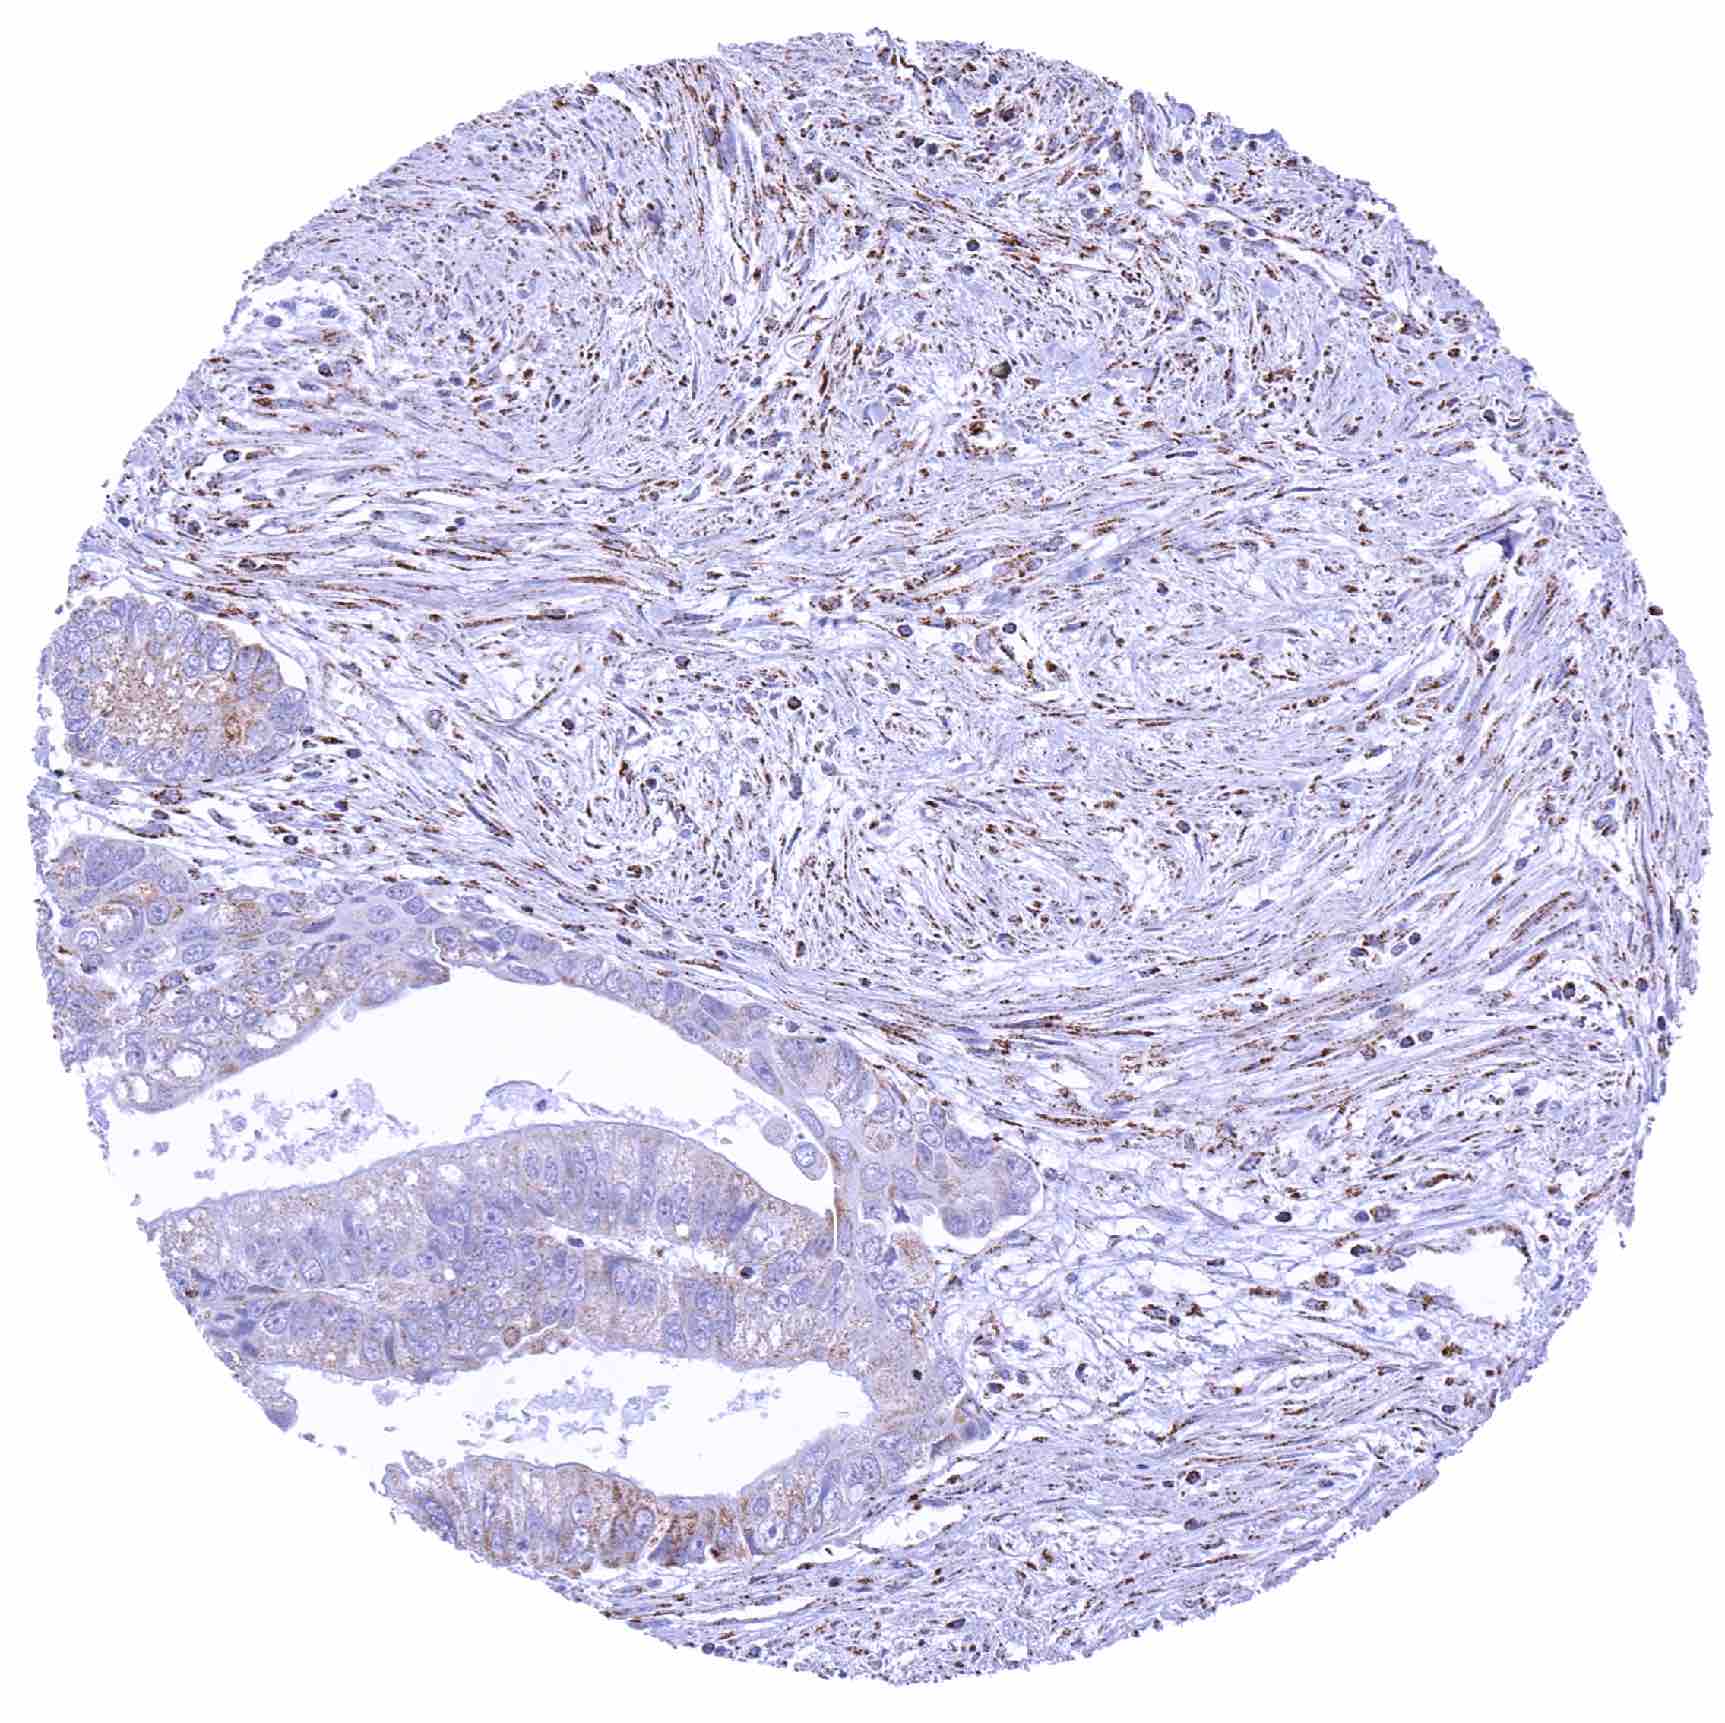

Renal pelvis – Muscle-invasive urothelial carcinoma displaying only a faint SDHA staining of tumor cells